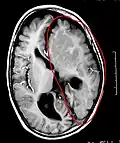

-

Cerebro enfermo, antes de la hemisferectomía